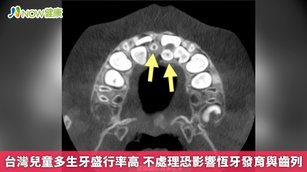

台灣兒童多生牙盛行率高 不處理恐影響恆牙發育與齒列

2026-02-23 19:29:585歲4個月的小琳(化名)日前在他院牙科檢查時,發現口內疑似有多生牙,於是轉診至奇美醫療財團法人奇美醫院兒童牙科門診接受進一步檢查。經口腔檢查後發現小琳除了有多顆嚴重蛀牙外,還有2顆多生牙,分別為正向與逆向生長。考量到小琳年齡尚小、齲齒範圍大以及治療配合度等因素,經與家屬充分討論後,最終決定進行全身麻醉,拔除2顆嚴重蛀牙的乳門齒以及2顆多生牙。術後恢復良好,2週順利拆線,目前持續定期回診追蹤。